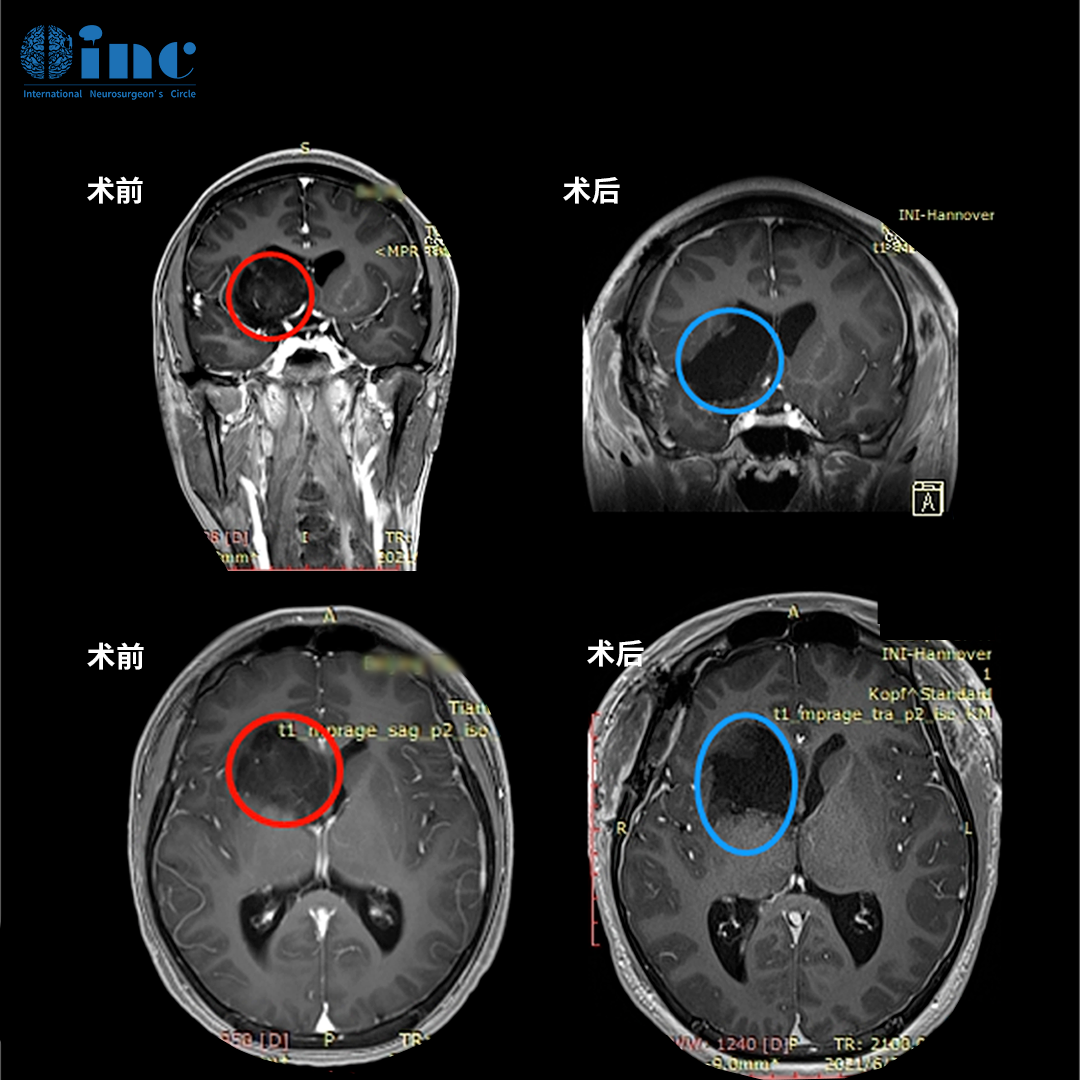

2019年,INC德国巴特朗菲教授曾4次来华,并在国内协作的三甲医院(苏州大学附属第一医院、苏州大学附属儿童医院、浙江大学医学院附属邵逸夫医院、无锡市第二人民医院等)开展疑难手术示范等,成功展示了多例在脑干、颅底、功能区等复杂病变(包括脑肿瘤/脑海绵状血管瘤/脑血管病变等)的全切及近全切手术之作。INC巴教授2019来华疑难手术示范掠影

2021年5月,INC排除万难推进“中德国际项目交流”,巴特朗菲教授来华进行学术交流及疑难手术示范。在上海市疫情防控办、江苏省卫建委、江苏省疫情防控办等政府相关部门的大力协助下,INC德国巴特朗菲教授来华计划得以成行,此次医学交流和疑难示范手术期间,两国医学专家同台手术,在救治疑难病症患者的同时,促成了中外神经外科之间的正常互动。

2021巴教授来华疑难手术示范掠影2022作为江苏省卫生支撑计划中德国际合作交流项目,INC国际神经外科医生集团旗下组织世界神经外科顾问团(WANG)成员、世界神经外科联合会WFNS教育委员会主席、德国INI国际神经学研究所Helmut Bertalanffy(汉莫特·巴特朗菲)教授受邀再次来华学术交流及疑难手术示范。在INC合作的国内三甲医院——苏州大学附属儿童医院及苏州独墅湖医院,巴特朗菲教授与国内专家同台示范手术,在救治疑难病症患者的同时,切磋手术技巧、学术交流讲学,推进中外神经外科之间的良性互动。

2022年巴教授来华疑难手术示范掠影